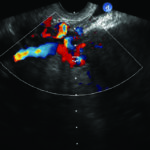

Fig. 1: Examen con Doppler color por vía transvaginal, demostrando dilatación de las venas utero ováricas del lado izquierdo.

Hallazgos imagenológicos. En el eco Doppler ginecológico por vía transvaginal se observa varicocele pelviano (Fig. 1). La vena ovárica derecha mide 3.8 mm, y la izquierda, ectásica, 7.4 mm (Fig. 2). En el eco Doppler abdominal se visualiza la vena renal izquierda, de 3.1 mm en topografía del compás aorto-mesentérico y 8.1 mm en el segmento proximal al riñón izquierdo, con una velocidad 50cm/s en el compas y 30cm/s en el segmento proximal al riñón. El estudio corresponde en primera instancia a un síndrome de Nutcracker (Fig. 3).